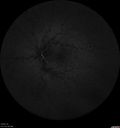

25 year old man with 1 week vision loss 20/16 OD 20/100 OS - CRVO

Heterozyrous for Factor V Leiden - Required 3 years of Lucentis - VA improved to 20/30. Able to stop therapy